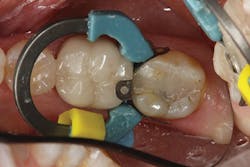

The contouring and primary anatomy can be placed with a flame-shaped fine diamond. Next, the occlusion is checked and refined on the restoration. Finally, the restoration can be polished easily with a two-step technique. I like to use polishing cups so I can polish both the occlusal and interproximal without having to change to a different polishing point. I first use Enhance (Dentsply Sirona), which can help shape as it polishes, and the final high shine is placed with the PoGo cup (Dentsply Sirona; figure 4).